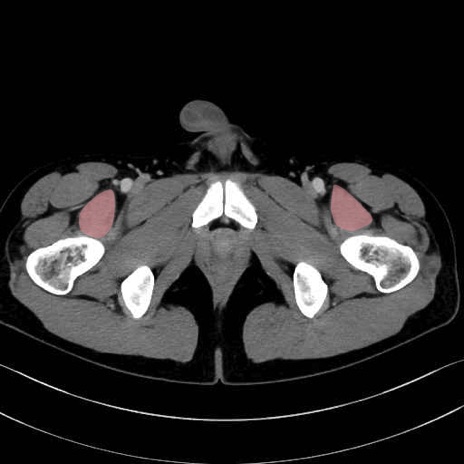

内閉鎖筋 (Obturator internus)